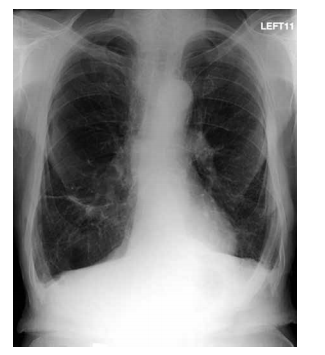

A imagem mostrada a seguir é observada em qual das seguintes doenças?